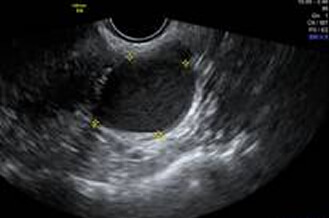

卵巢巧克力囊腫